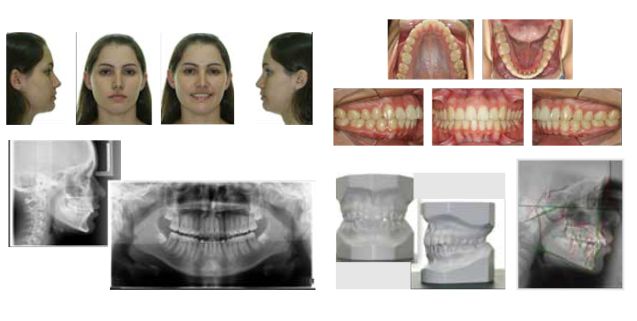

DOCUMENTAÇÃO ORTODÔNTICA

Laudos e Análises Radiográficas

Modelos de Estudo em Impressora 3D

Fotografias Bucais (Extra e Intra)

Documentação 100% Digital (Sistema IDoc)